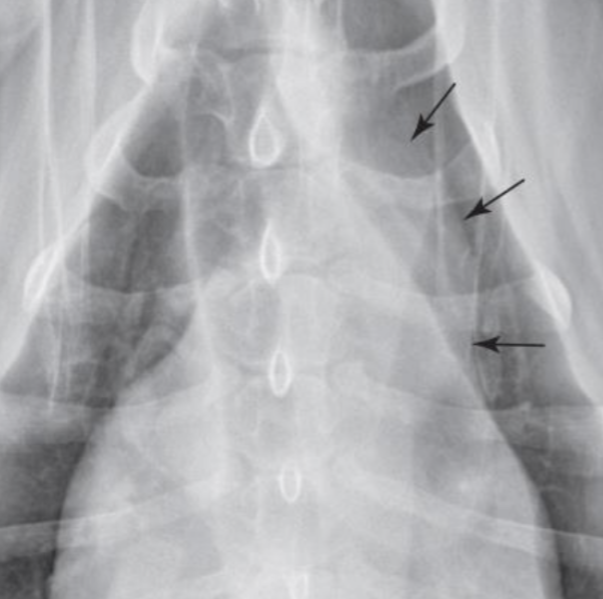

| mPA enlargement |

|---|

| 1์ ๋ฐฉํฅ์ bulging โReversed D signโ (์ค๋ฅธ์ชฝ ์ฌ์ฅ๋ณ) |

| PH (PTE, HW, PDA) PS |

![]() ![]() |